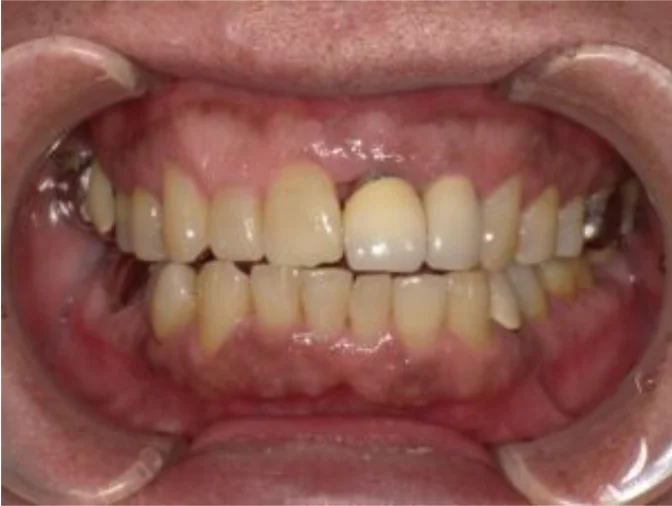

Before

After

口蓋隆起を避けた設計で金属床義歯を製作(60代男性)

約1年 / 総額350,000円リスク・副作用:・残存歯、義歯ともに定期的なメンテナンスが必要です ・義歯を清潔にご使用いただくため、毎日の義歯洗浄剤の使用を推奨します